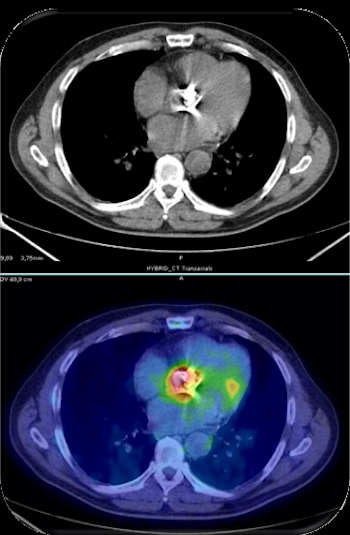

Given our common background, the response can only be PET. FDG-PET is indeed the single area of MI with the largest clinical application at present, especially in oncology, and holds further potential for developments. In the future, it's easy to predict that the use of other radiopharmaceuticals will widen the application in many clinical settings, from neurology to infective disease.

Yes, it will be a challenging time ahead, but a bright future exists for our field, especially if we are able to drive the process. We know that in vivo analysis of molecular expression at a cellular level allows an earlier diagnosis. This is already in clinical practice with PET, which has dramatically changed our capability to assess disease activity and extension. The next steps for MI include the synthesis of new radiotracers to increase specificity. Furthermore, a combination of different tracers and approaches will allow us to depict the exact molecular profile of the disease, leading to personalized therapies.